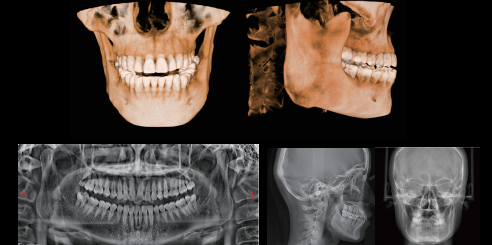

Múltiples Imágenes

Soporte CT / PAN / CEF.

Mediciones Cefalométricas Laterales

En comparación con las radiografías cefalométricas bidimensionales tradicionales, los cefalogramas laterales en CBCT pueden reflejar mejor la verdadera morfología craneofacial. Con una mayor precisión en la identificación de puntos de referencia y la medición de distancias de líneas, puede evitar la distorsión de los datos de medición del paciente causada por la superposición, la imagen borrosa y la asimetría facial de estructuras anatómicas bidimensionales.

IA + Medición CEF (Opcional)

La red neuronal se entrena con megadatos, que identifican automáticamente puntos de referencia anatómicos de ortodoncia, dibujan estructuras anatómicas y generan informes de medición de acuerdo con los métodos de medición seleccionados.